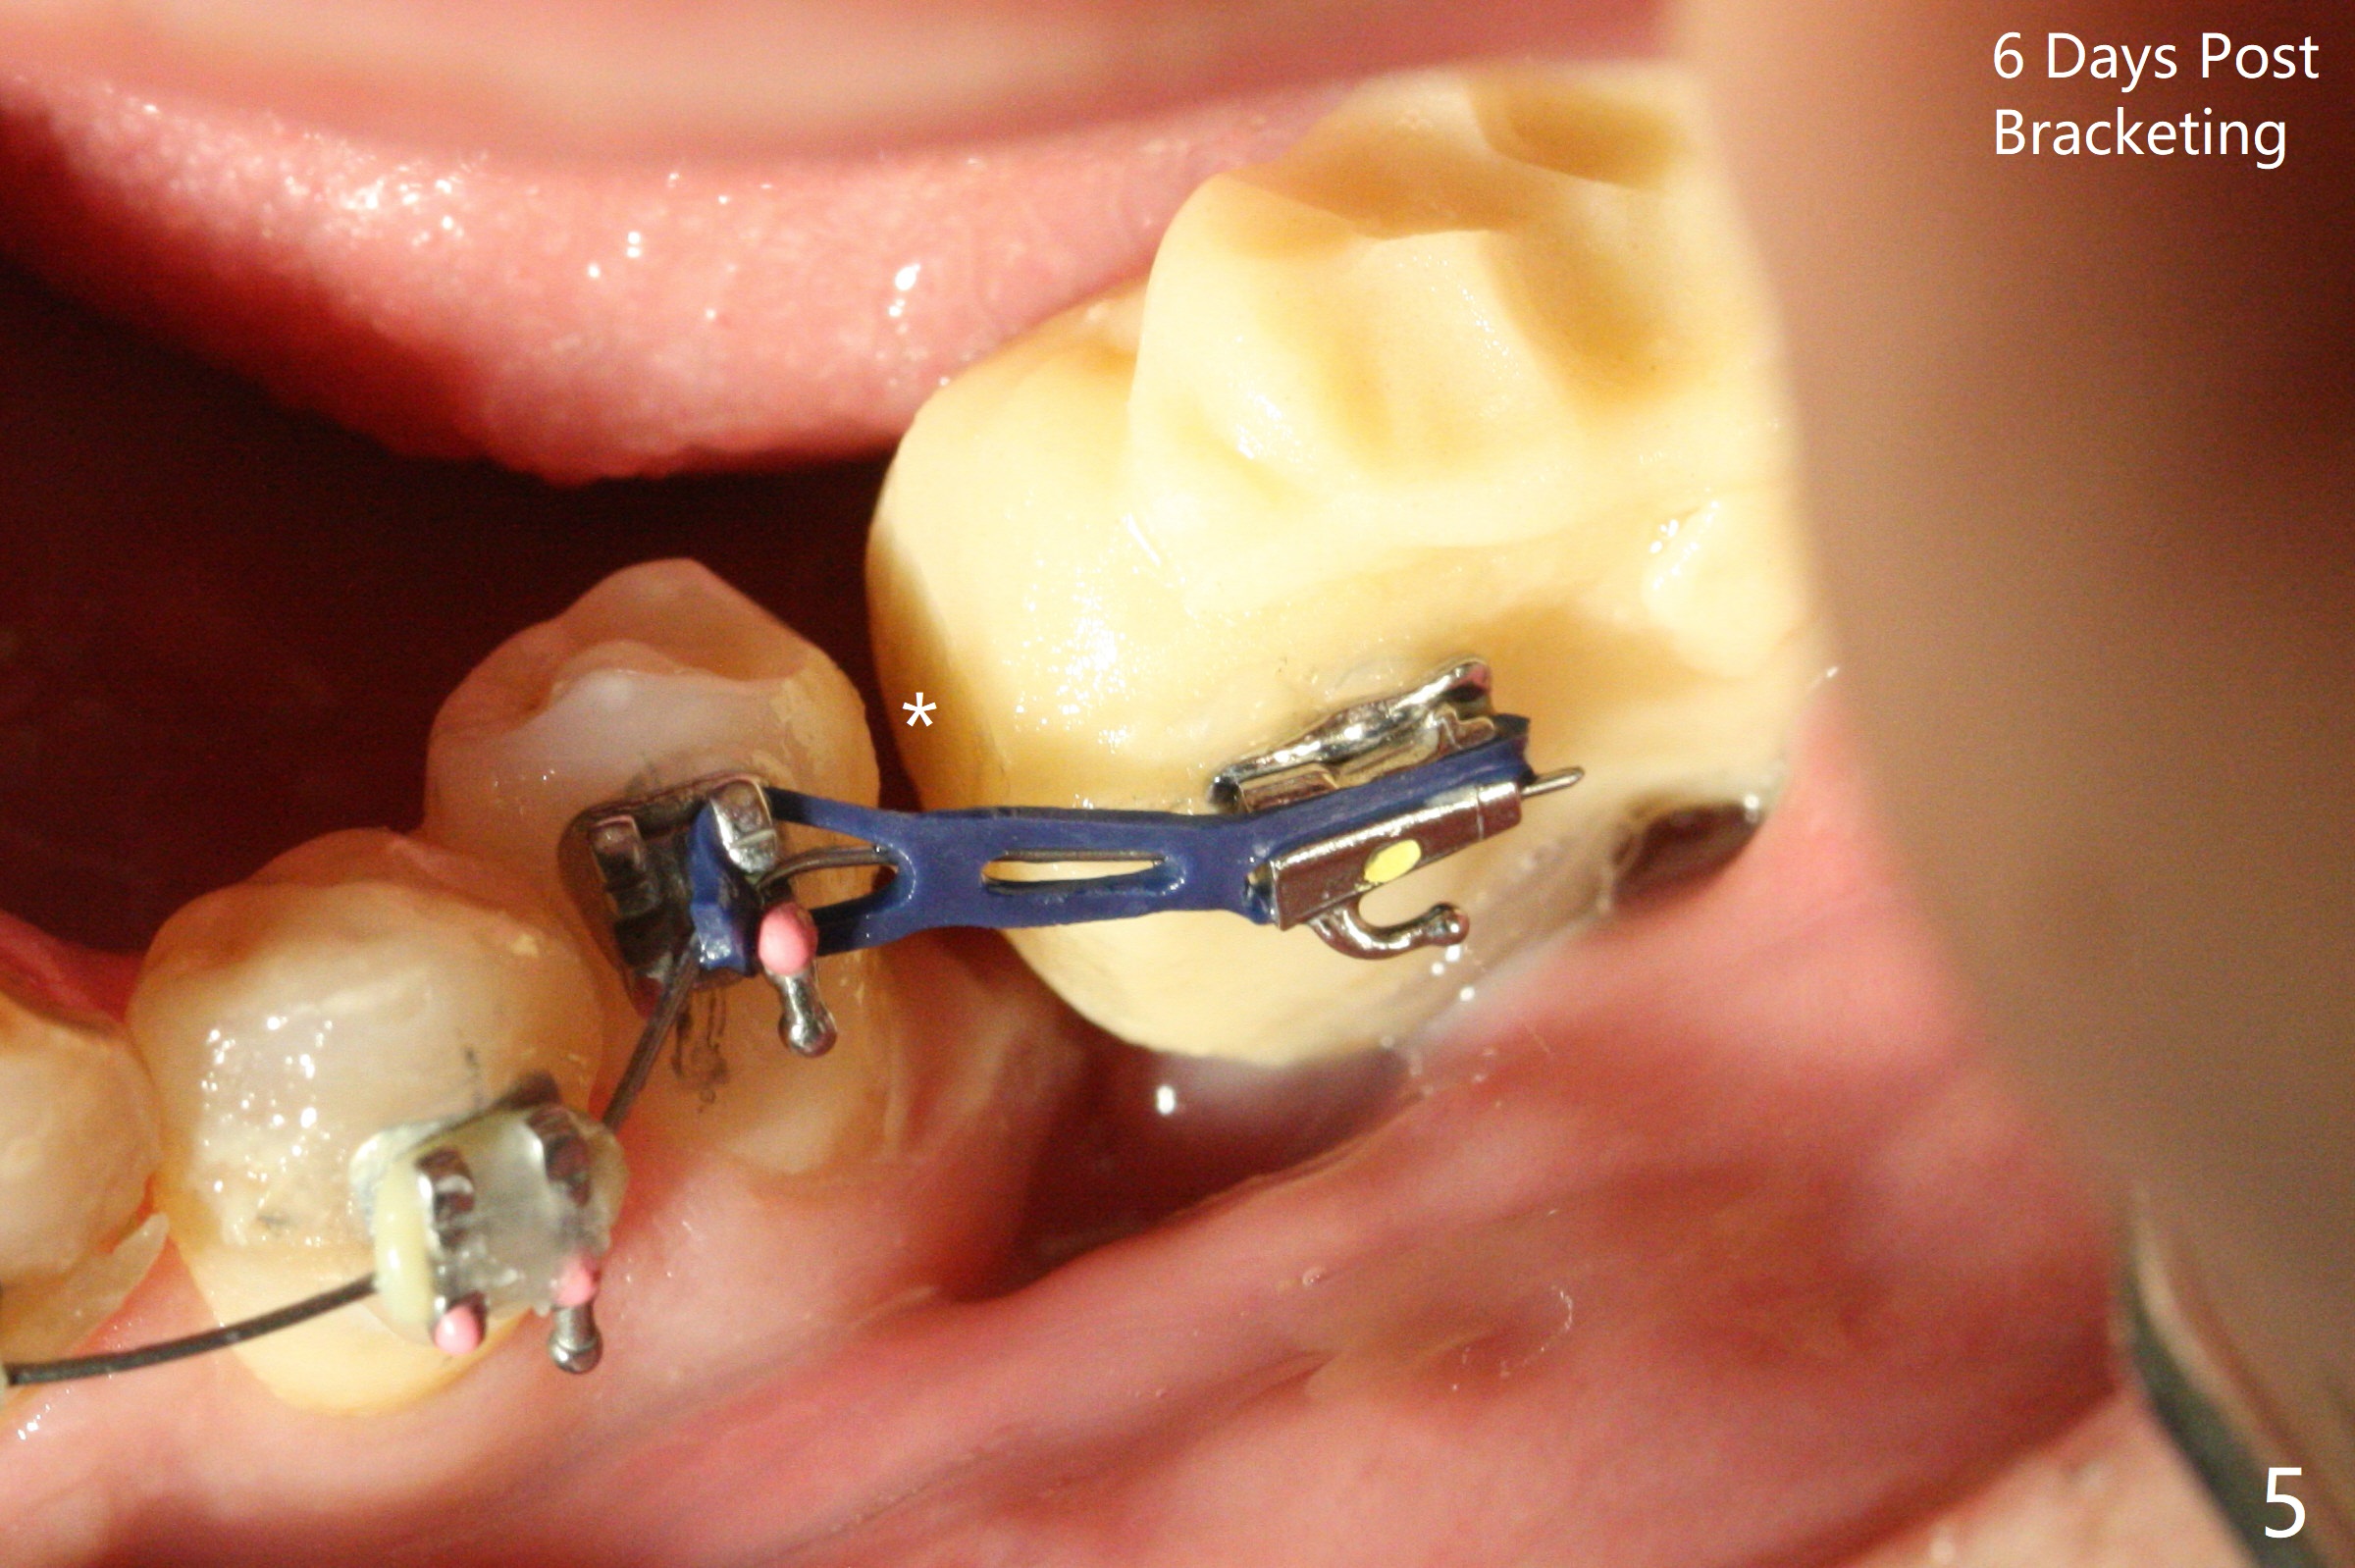

Two weeks post provisionalization over implants at #18 and 19 (4.5 months postop), acrylic is added to the provisional (Fig.1 *) and composite is placed on the other side (Fig.2 *) for clearance (Fig.3). Six days post bracketing, the diastema between LL5 and 6 decreases (Fig.4 between arrows, as compared to Fig.3), suggesting uprighting and distalization of the affected tooth. The diastema increases by trimming the mesial surface of LL6 provisional (Fig.5 *) prior to power chain placement. More acrylic is added to the occlusal surface of LL 6 and 7; more composite to that of UR3 (as compared to Fig.2) for clearance. Power chains change every week. LL5 is uprighted and distalized 1.5 months post banding (Fig.6,7 (14 niti)). Anterior brackets will be placed to correct LL2 cross bite next visit. Three weeks post open coil spring (5 months post initial banding), there is a space between LL2 and 3 (Fig.8) and between LL3/4 (Fig.9). The latter reduces instantly post power chain between LL3 and 6 (Fig.10). There is enough space for LL2 and sling shot is used to correct the cross bite 6.5 months post initial banding (Fig.11). The cross bite is corrected in 1.5 months after occlusal clearance is established (Fig.12). The lower left alignment is within normal limit, although in cross bite with the opposing dentition, immediate post molar crown cementation (Fig.13).